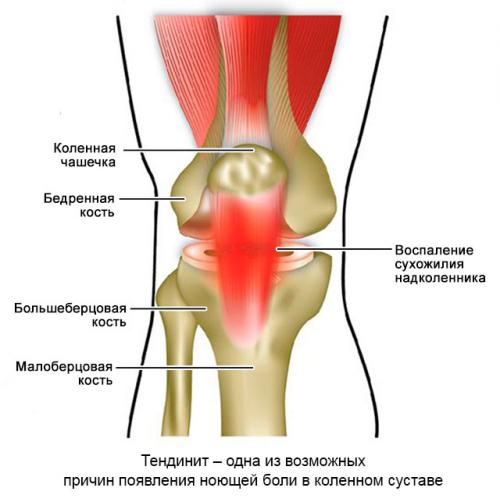

- Тендинит.

Тендинит собственной связки надколенника